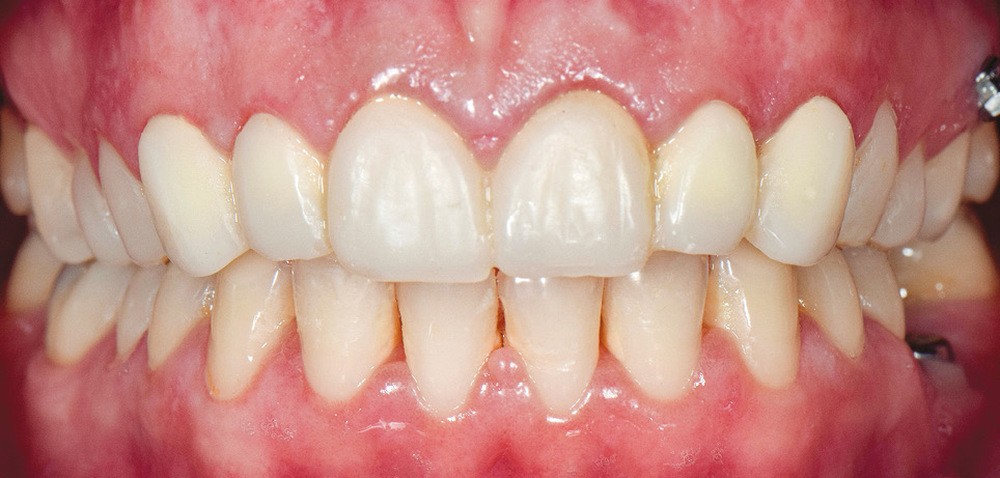

À l’examen endobuccal (fig. 1), une inflammation marginale et papillaire sur un parodonte de biotype fin est visible. Une gingivite généralisée induite par la plaque bactérienne est donc diagnostiquée.`

La ligne du sourire est inversée, malgré une perception atténuée par la présence de deux couronnes à armature zircone sur 11 et 21 réalisées une dizaine d’années auparavant. On note une irrégularité et une asymétrie de forme des festons gingivaux, ainsi qu’une dysharmonie de forme des incisives et canines quant à leur proportion.